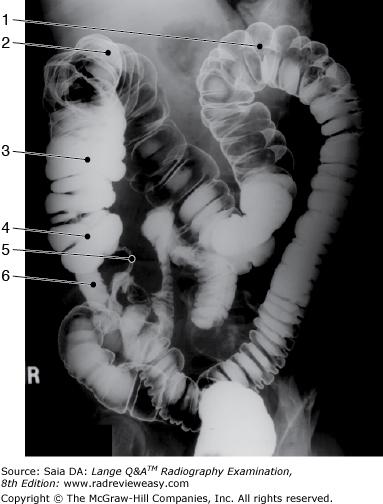

The radiograph pictured in Figure A may be used to evaluate

1. polypoid lesions.

2. the lateral wall of the descending colon.

3. the posterior wall of the rectum.

1 and 2 only